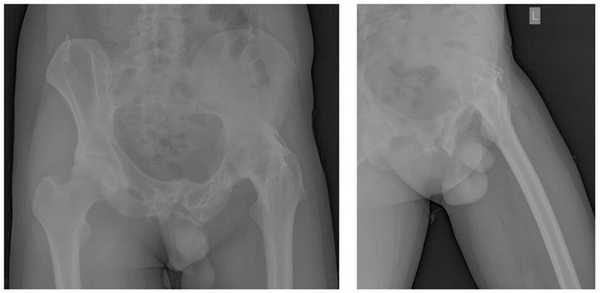

Пациент П. 64 лет на протяжении 3 лет отмечает выраженные, постепенно прогрессирующие боли в области правого тазобедренного сустава. Обратился в К+31 в мае 2017, осмотрен ортопедом, выполнены рентгенограммы тазобедренных суставов. Диагностирован коксартроз справа 3 ст, слева 2 ст. Рекомендовано оперативное лечение - тотальное эндопротезирование правого тазобедренного сустава.

Учитывая возраст пациента решено использовать протез бесцементной фиксации фирмы Zimmer, пара трения керамика\керамика.

Произведено предоперационное планирование, рассчётные размеры: ножка Avenir 6, чаша Trilogy 60, керамический вкладыш с внутренним диаметром 40 мм, керамическая головка 40 мм.

В мае 2017 выполнено оперативное вмешательство, тотальное эндопротезирование правого тазобедренного сустава.